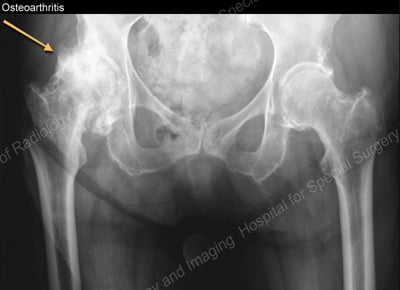

While imaging of the joint is not always required for a clinical diagnosis of OA, different forms of imaging are often helpful. In later stages, OA can be seen on X-ray images.

However, X-ray images do not show the early changes in a joint associated with OA or in the tissue surrounding the joint. These changes typically require other imaging techniques, such as MRI, CT scan, or ultrasound can be useful to accurately evaluate the structures in the joint.

Anteroposterior (font-to-back) X-ray showing severe, late-stage OA of the right hip joint (seen on the left side of the image)